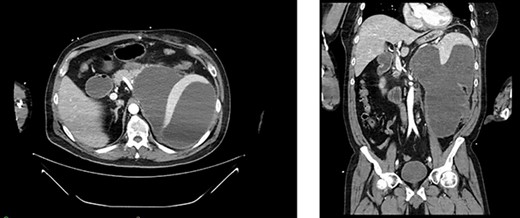

Left renal mass measuring 11 × 9 × 7cm in transverse (left) and coronal (right) planes.

A 52-year-old, previously healthy, Caucasian male presented to the emergency department (ED) with chief complaints of gross hematuria, abdominal pain, vomiting, diarrhea and left flank pain for 3 days. He had neither family history of cancer nor history of exposure to ionizing radiation, arsenic, thorium dioxide or vinyl chloride. He reported exposure to chemical tankers 10 years prior and had recent occupational exposure to paint-thinning agents. Urinalysis on admission showed large blood with later cytology significant for atypical epithelioid cells concerning for neoplasm of the kidney or bladder. Subsequent contrast-enhancedcomputed tomography (CT) of the abdomen revealed an 11-cm left renal mass, 2-cm para-aortic lymphadenopathy and possible invasion of the tail of the pancreas (Fig. 1). He was then referred to urology for evaluation and to discuss treatment options.